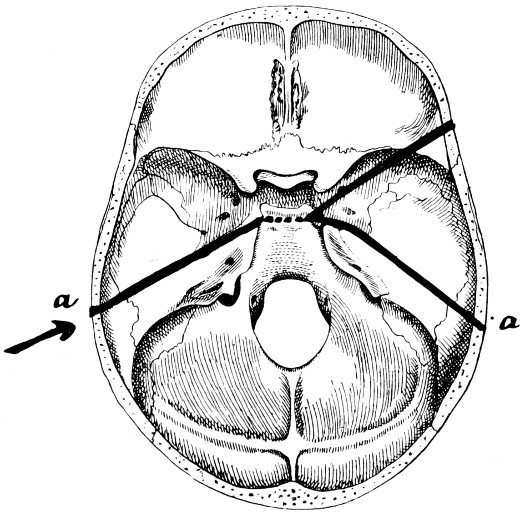

32-37. The lines pursued by basic fractures 83-8

38 A and B. To illustrate the probable source of profuse hæmorrhage from the ear 97